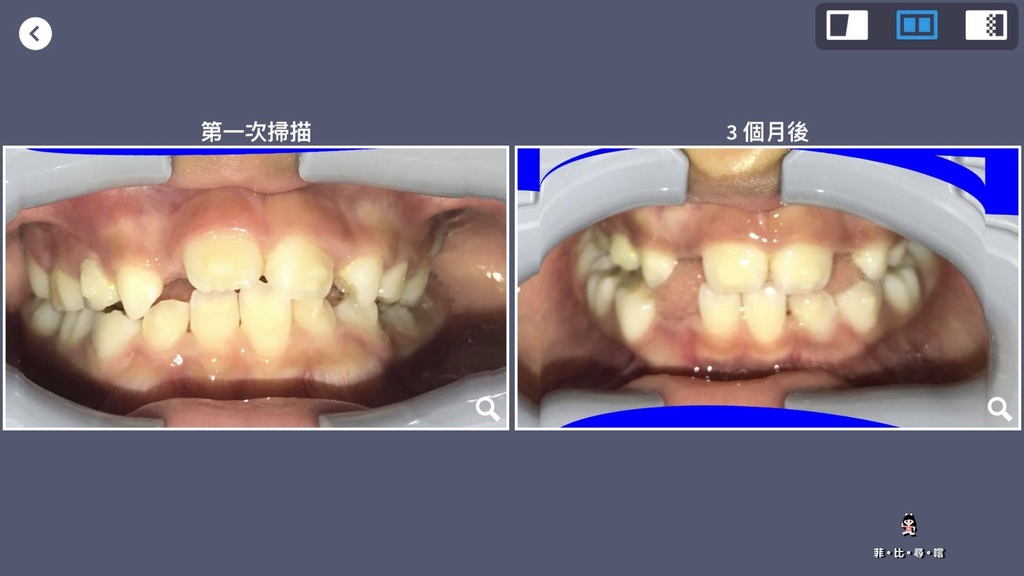

小菲菲目前矯正了3個月

和第一次掃描作比對,很明顯門牙變正了,門牙右側已弓出空隙了

右下空出來的,是正換了乳牙,哈!

每天看不覺得有什麼變化

一看掃描記錄就清清楚楚了~

真的是很方便的設計呢!!